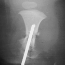

TREATMENT: The patient initially underwent a corrective tibial osteotomy and Boyd amputation of right foot. The postoperative course was complicated by the development of a nonunion at the osteotomy site necessitating resection of the pseudarthrosis with placement of K-wires. Following this, she did well ambulating with the use of a below-knee prosthesis.